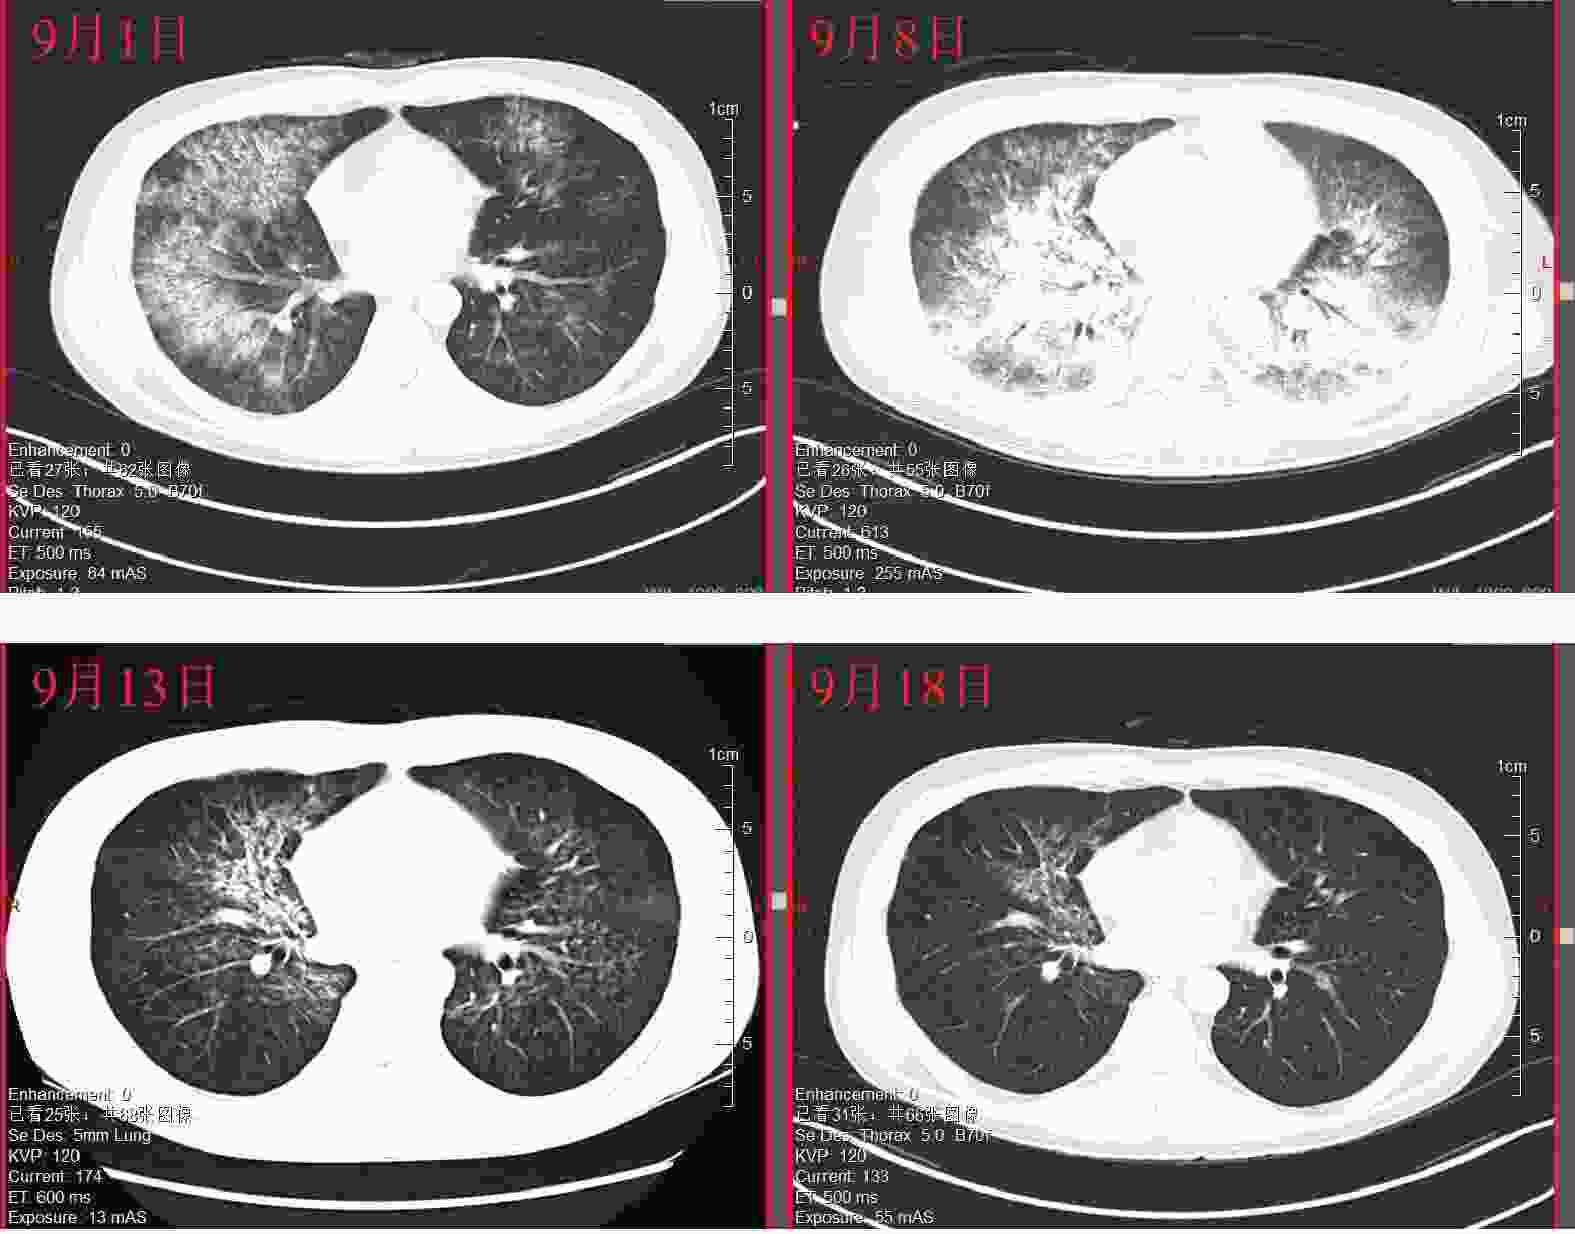

• 患者入院前在门诊完成各项检查,血常规、尿常规、便常规、手术感染八项、凝血功能及肝肾功能正常,胸片无异常。8月31日9:00入院,血压、心率、体温正常,10:00和18:00给予G-CSF注射液300 μg皮下注射各1次,无其他合并用药。9月1日6:00给予G-CSF注射液300 μg皮下注射1次,患者诉咽部不适,有血丝咳出,7:47急查凝血六项,未见异常。9:30查体,血压100/65 mmHg,血氧饱和度94%,双肺呼吸音清,10:37急查胸部CT,两肺见弥漫分布片状密度增高影及磨玻璃影(图1),提示两肺渗出,排除呼吸道感染,咽喉鼻腔出血和肺栓塞,12:00综合患者咯血及肺部影像学表现,考虑有DAH,病情较重,停G-CSF注射液,停三级护理改一级护理,给予心电、血压、血氧饱和度监测,持续低流量吸氧,根据血氧饱和度调整,给予注射用甲泼尼龙80 mg q12 h,注射用奥美拉唑40 mg q12 h,维生素K1注射液10 mg q12 h。9月2日8:00,患者血氧饱和度低,在90%~94%之间波动,心率110次/min,血压正常,呼吸颦促(约40次/min),改为高流量吸氧;9:16急查床旁胸片,提示肺部炎症较昨日明显加重,给予注射用甲泼尼龙500 mg q12 h、静注人免疫球蛋白25 g冲击治疗,同时给予重组人凝血因子Ⅶa止血,给予注射用艾司奥美拉唑40 mg q12h预防应激性溃疡,更换常压高流量氧疗仪,后血氧饱和度维持在97%~98%,呼吸频率降至25次/min左右。9月3日9:00患者仍间断咯血,血红蛋白下降至98 g/L,血氧饱和度94%,床旁胸片提示左肺病灶较昨日略加重,继续500 mg甲泼尼龙冲击,加用矛头蝮蛇血凝酶加强止血,高流量给氧条件下加用面罩吸氧;20:00血压下降至87/50 mmHg,紧急输注红细胞后血压升至97/59 mmHg,21:00咯血加重,每间断约10 min就要吐出约20 ml鲜红色血液,继续输注红细胞、血浆400 ml;23:45给予全麻下床旁气管插管,呼吸机辅助呼吸,同时置入胃管,持续胃肠减压、吸痰治疗。胃管引流出鲜红色液体约50 ml,行床旁气管镜检查,镜下见左右主支气管内大量鲜红色血性液体涌出,给予镜下吸引并局部使用去甲肾上腺素稀释液止血,继续输血、止血治疗。9月4日,患者镇痛镇静持续俯卧位通气状态,经口气管插管持续呼吸机辅助呼吸,监护显示体温36 ℃,心率98次/min,血压111/75 mmHg,血氧饱和度91%,输注悬浮红细胞2 U、普通冰冻血浆400 ml,将激素减量至注射用甲泼尼龙120 mg q12 h,考虑血浆置换治疗。9月5日和9月6日给予床旁血浆置换。9月6日患者镇痛镇静持续俯卧位通气状态,经口气管插管持续呼吸机辅助呼吸,监护提示心率89次/min,血压146/60 mmHg,血氧饱和度96%,血浆置换后气道出血减少,血氧饱和度改善,病情好转,将激素减量至注射用甲泼尼龙80 mg q12 h,并限液利尿。9月7日行气管检查见左右主气管及各级支气管开口通畅,可见陈旧性血性分泌物及血栓附着,各分段支气管开口通畅,无新鲜出血。9月8日患者血氧饱和度明显改善,肺泡出血减少,充分评估后脱机拔管;复查胸部CT,两肺见弥漫分布片状密度增高影及磨玻璃高密度影(图1),提示双肺弥漫性肺出血。9月9日患者神志清楚,经鼻高流量氧疗,监护提示体温36 ℃,心率67次/min,血压124/82 mmHg,血氧饱和度97%,激素调整为注射用甲泼尼龙每天早80 mg、晚40 mg,继续吸氧、雾化、抗感染、辅助排痰等治疗。9月11日患者病情平稳,经鼻高流量氧疗,血氧饱和度99%,复查肺部CT继续好转,注射用甲泼尼龙减量为40 mg q12 h。9月13日复查胸部CT,两肺见片状密度增高影及磨玻璃密度影较前减少(图1),提示双肺出血较前减轻。9月14日患者不吸氧状态下血氧饱和度98%,未再诉咽颈部疼痛,注射用甲泼尼龙减量为20 mg q12 h。9月18日复查胸部CT,两肺渗出阴影较前明显减少(图1),提示双肺出血较前明显好转,停用静脉激素,予以醋酸泼尼松片25 mg qd序贯口服治疗。9月20日患者情况稳定出院。